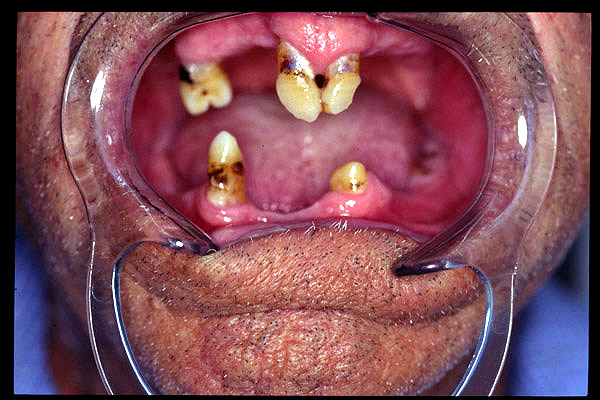

CM Unicos dientes remanentes: caninos superiores